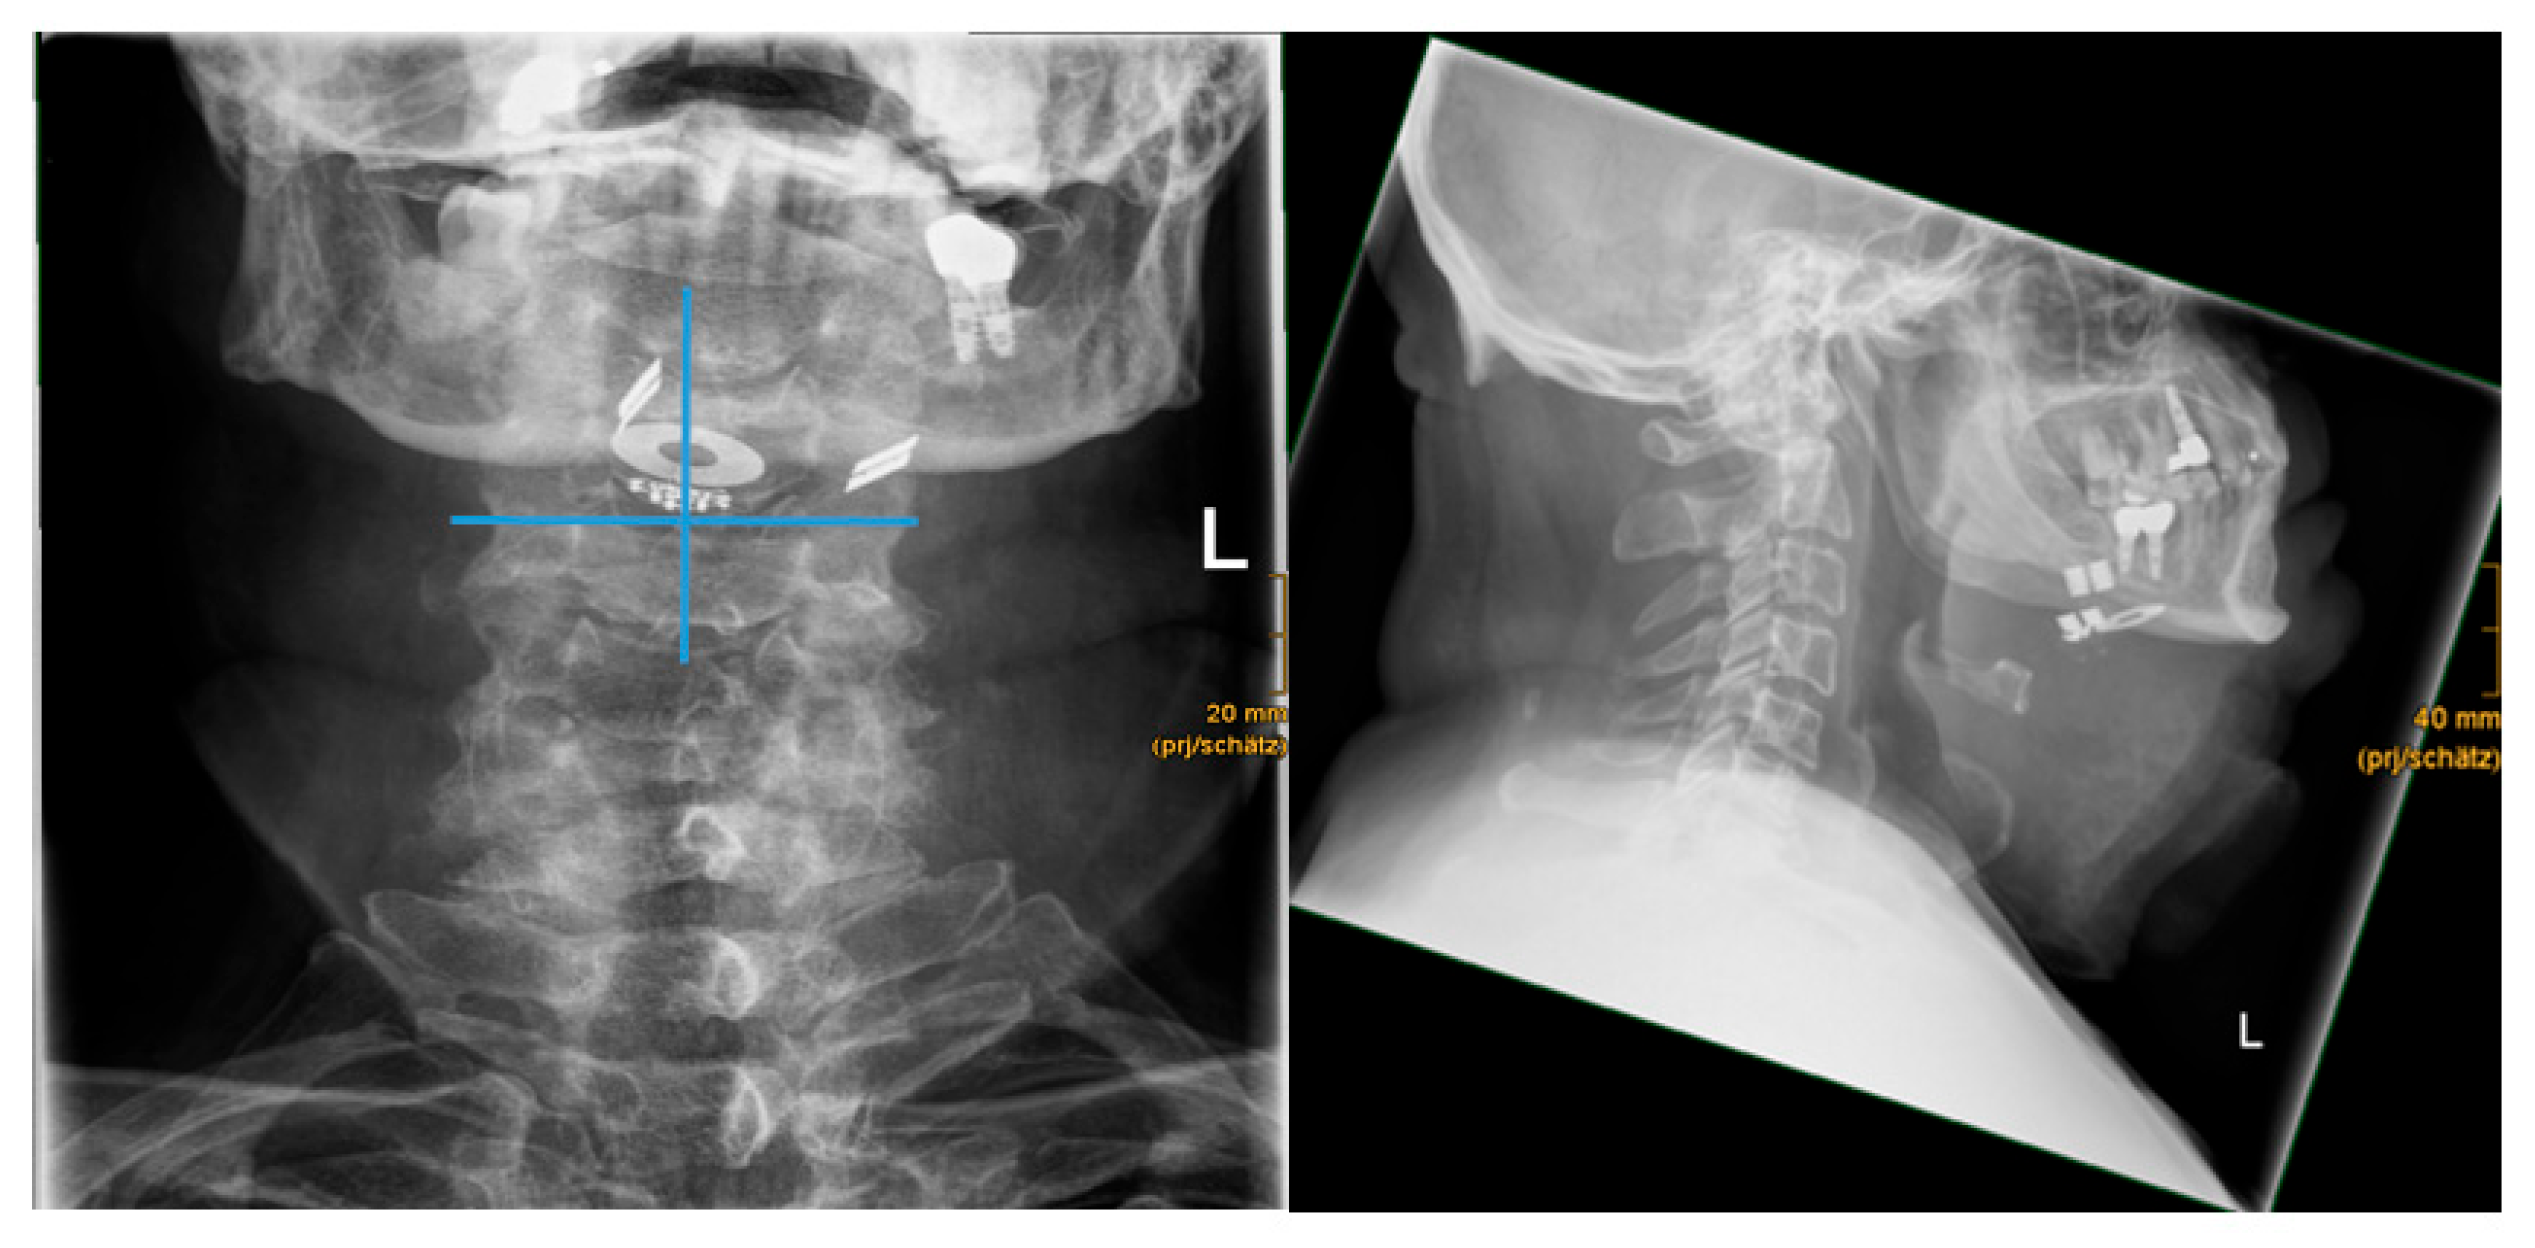

| Patient | AHI | BMI | previous implants (e.g. dental implant) | postoperative CT performed | artifacts CT | artifacts CT severity level | artifacts X-ray | postoperative XRAY performed | mandibular length (in mm) | distance mandibula plane-to-hyoid (in mm) | distance chin to hyoid (in mm) | mean distance hyoid to paddle electrode (in mm) | 1_right side_distance hyoid to paddle electrode (in mm) | 2_left side_distance hyoid to paddle electrode (in mm) | Difference right-left side (in mm) | alignement paddle electrode symmetry/asymmetry | angle hyoid-stimulation antenna (in °) | electrode position proximal/distal to mandible | electrode position proximal/distal to hyoid |

| 1 | 33 | 26 | yes | yes | yes | moderate | no | yes | 87,3 | 28,7 | 56,4 | 15,2 | 7,9 | 22,6 | -14,7 | asymmetry | 64,9 | proximal | proximal |

| 2 | 47 | 30 | yes | yes | yes | strong | no | yes | 94,1 | 45,7 | 57,0 | 19,0 | 18,7 | 19,3 | -0,6 | symmetry | 70,4 | proximal | proximal |

| 3 | 51 | 28 | yes | no | n/a | n/a | no | yes | 109,3 | 32,6 | 48,4 | 17,2 | 15,0 | 19,3 | -4,3 | asymmetry | 60,3 | proximal | proximal |

| 4 | 64 | 31 | yes | yes | yes | moderate | no | yes | 113,9 | 55,3 | 76,2 | 25,9 | 18,8 | 32,9 | -14,1 | asymmetry | 73,8 | proximal | proximal |

| 5 | 37 | 32 | yes | yes | yes | strong | no | yes | 93,2 | 23,9 | 54,5 | 15,4 | 13,9 | 16,9 | -3,0 | asymmetry | 35,3 | proximal | proximal |

| 6 | 52 | 25 | yes | yes | yes | moderate | no | yes | 86,0 | 20,3 | 47,1 | 15,8 | 15,6 | 16,0 | -0,4 | symmetry | 19,0 | proximal | distal |

| 7 | 28 | 28 | yes | yes | yes | moderate | no | yes | 102,0 | 36,7 | 64,3 | 16,4 | 14,4 | 18,3 | -3,8 | asymmetry | 40,7 | proximal | distal |

| 8 | 16,5 | 34 | yes | yes | yes | strong | no | yes | 122,3 | 32,1 | 77,9 | 12,5 | 18,4 | 6,6 | 11,8 | asymmetry | 39,9 | proximal | distal |

| 9 | 32 | 29 | yes | yes | yes | moderate | no | yes | 110,5 | 40,3 | 69,4 | 16,6 | 14,9 | 18,2 | -3,2 | asymmetry | 63,5 | proximal | proximal |